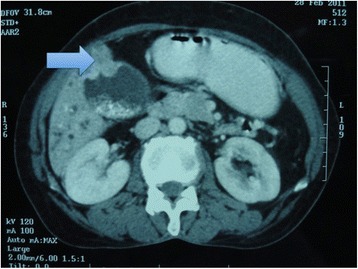

CT scan showed moderate dilatation of the extra and intrahepatic biliary radicles, cholelithiasis with suspicious thickening of the gall bladder wall at the fundus, and a distal CBD stricture. There was no evidence of any distant metastasis (Fig. 1).